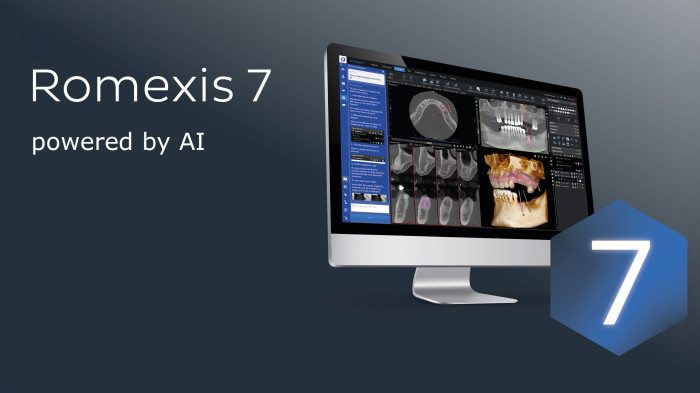

Disfrute de la combinación perfecta entre la tecnología de rayos X moderna y el soporte de software inteligente: la tecnología de imagen KaVo ProXam y las herramientas basadas en IA de Romexis permiten obtener imágenes que muestran más allá de lo obvio.